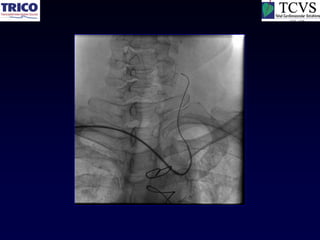

RCA CTO

Unprotected LMCA Stenting